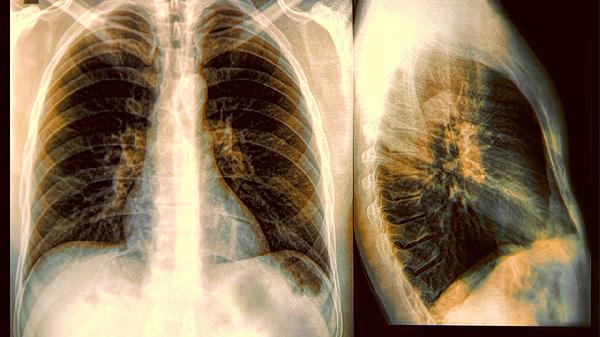

肺泡蛋白質(zhì)沉積癥胸部CT顯示雙肺彌漫性磨玻璃影,呈"鋪路石"樣改變。白肺在X線或CT上表現(xiàn)為雙肺廣泛均勻的白色陰影,肺紋理消失,常見于急性呼吸窘迫綜合征。